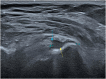

The rotator cuff is a group of four muscles and tendons surrounding the shoulder joint providing it strength and stability. The rotator cuff consists of the subscapularis, supraspinatus, infraspinatus and teres minor. Many shoulder complaints are caused by rotator cuff pathology such as impingement syndrome, tendon tears and other diseases e.g. calcific tendonitis. Diagnosis starts with clinical history and physical examination, after which imaging is often used to help confirm clinical findings depending on the differential diagnosis. The aim of the article is to review the frequently used imaging modalities to assess the rotator cuff and cuff-related disease, specifically focusing on radiography, ultrasonography and magnetic resonance imaging. This article will outline the advantages and disadvantages for each modality and illustrate typical radiological findings of common rotator cuff pathologies.